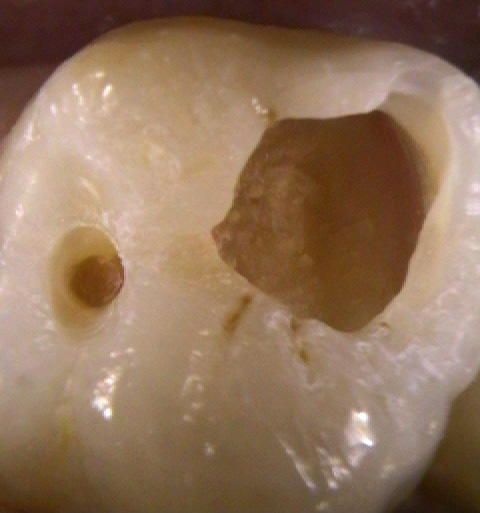

| C2象牙質の虫歯 | 虫歯除去後 | 治療後 |

|---|---|---|

|

入口は小さいのですが、中の象牙質まで大きく虫歯は進行していました。 |

麻酔を使用し、1回の治療で終わります。 |

神経の近くまで虫歯が進行すると治療後に痛みが止まらないことがあります。 |